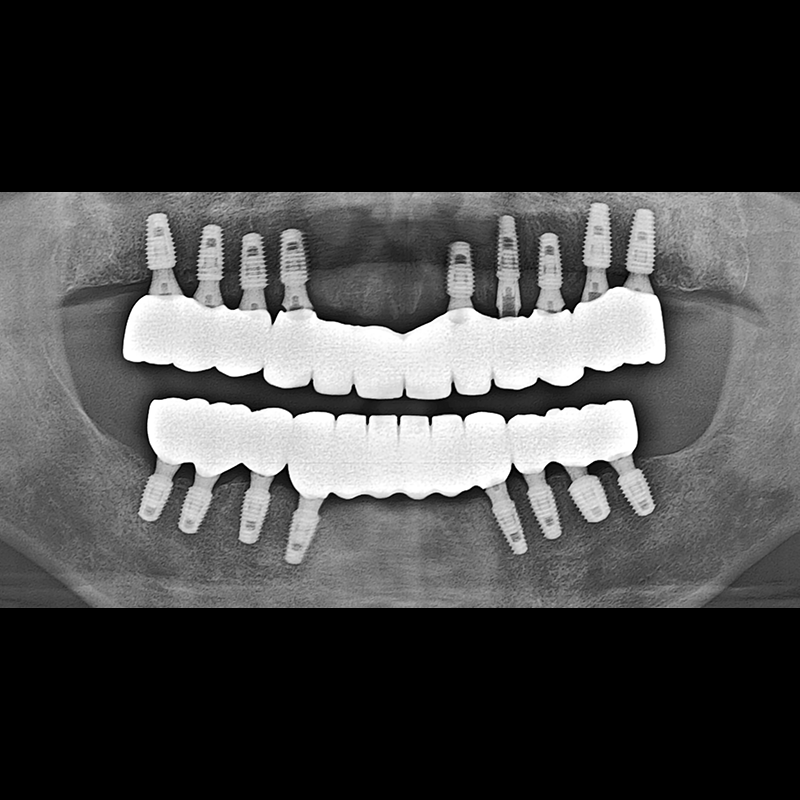

BEFORE AFTER

インプラント手術事例 2025.05.30

欠損した歯の部分と、生かしにくい歯の位置にインプラントを植立しました。